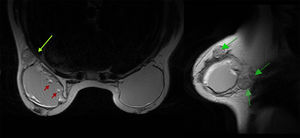

Mujer de 46 años con historia de melanoma dorsal izquierdo estadio IB de la AJCC en el año 2013. Durante el seguimiento se palpó una masa subcutánea de consistencia elástica, de aproximadamente 4cm en la región axilar izquierda. Con la sospecha de lipoma se realizó una ecografía (Esaote Mylab 25, sonda lineal de 10MHz), apreciándose una imagen hiperecogénica difusa en «tormenta de nieve» localizada en el tejido subcutáneo, de 5cm de diámetro mayor (fig. 1B). La paciente confirmó haberse implantado unas prótesis PIP en el año 2002. En este caso se realizó una resonancia magnética nuclear (RMN) mamaria, apreciándose rotura capsular de prótesis izquierda con siliconomas axilares y periprótesis (fig. 3).